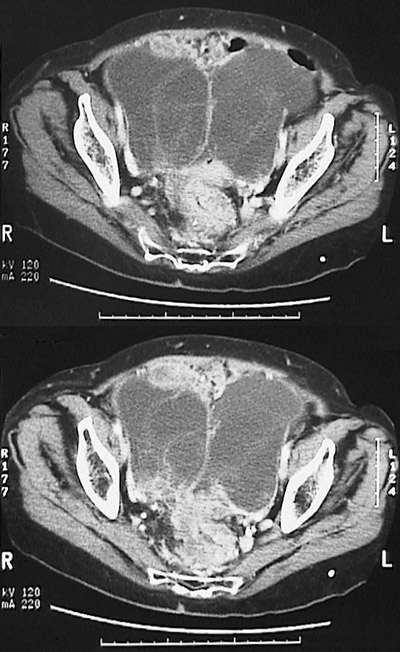

Click on the ovarian cystadenocarcinomas in the CT scan above:

This abdominal CT scan of the pelvis with contrast demonstrates bilateral ovarian neoplasms that abut in the midline. Note that these tumor masses are cystic and multiloculated. Cystadenocarcinomas can be bilateral. They can be serous or mucinous.